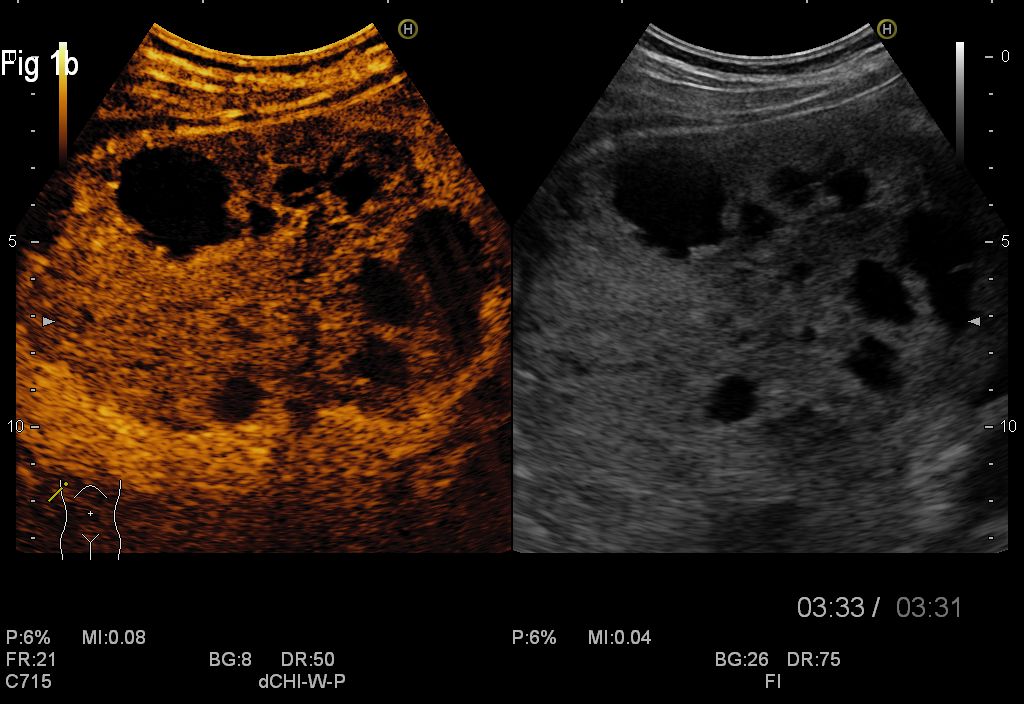

Conventional abdominal ultrasound revealed numerous well-demarcated masses in the right liver lobe, with internal septations and mixt content, transonic and hypoechogenic.

CEUS showed enhancement in the arterial phase and slow wash-out in the late venous phase at the periphery with central necrosis in some of the masses, which excluded the diagnosis of hydatid cyst and was suggestive for a malignant pattern.